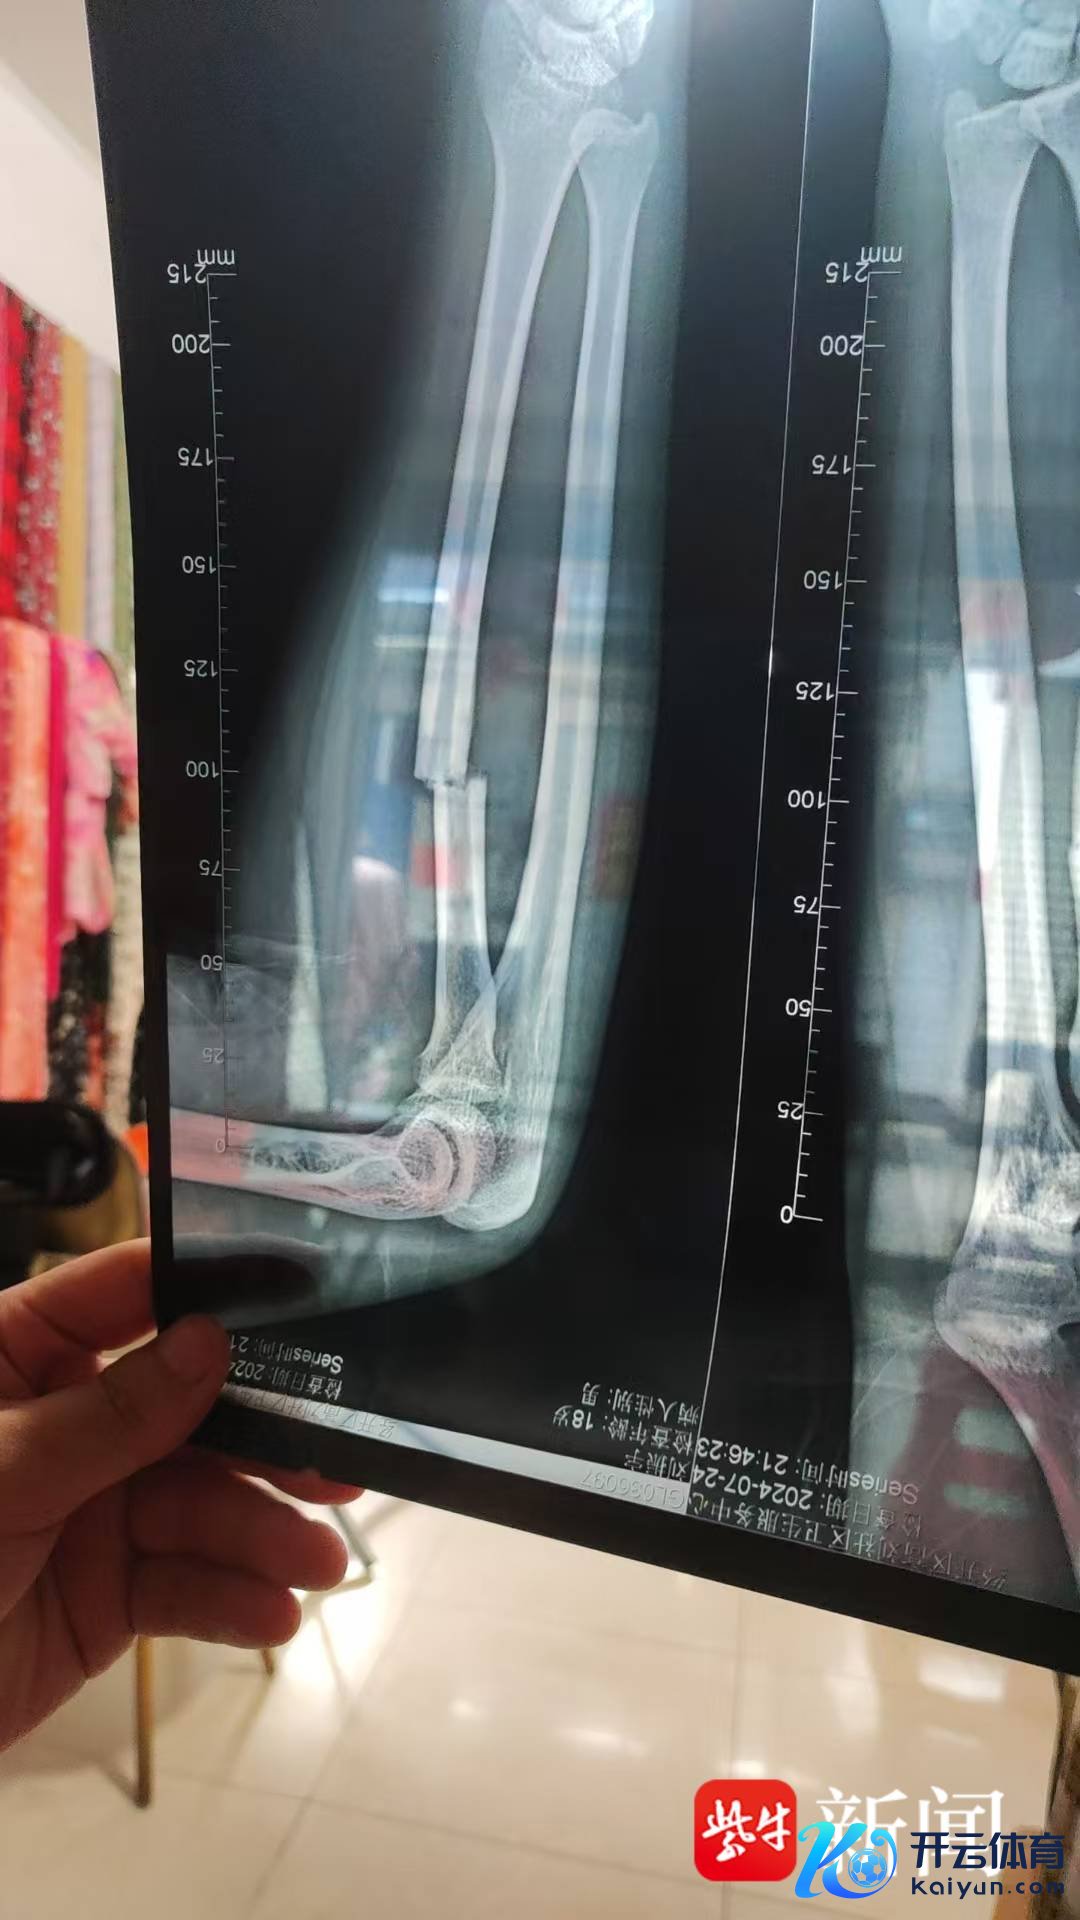

病院片子露馅小刘骨折

小刘告诉记者,该公路自行车是本年7月10日下单的,7月13日签收,车架竣工,轮胎和坐垫需我方装配。“这是我高考之后打暑期工,拿到第一个月工资后给我方买的礼物,花了1298元。”小刘说,7月24日晚,他出去夜骑,鄙人坡时,自行车龙头与轮胎衔接处忽然断裂,小刘栽倒在地。小刘被送医后,大夫会诊他的一条手臂是“错位性骨折”,如若作念手术需要好几万元,因手术费不少,小刘选拔保守调治。当晚,大夫对刘同学进行了石膏固定调治。凭据医嘱,刘同学需要依期去病院进行复诊,凭据复诊着力细目是否需要手术改良。目下刘同学处于不雅察期,因伤所致无法进行任何剧烈畅通。